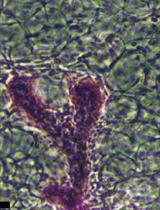

This protocol addresses a common challenge encountered when generating paraffin blocks from organoids cultured in BME. When fixation is performed directly on organoids embedded in BME, the matrix undergoes dehydration during processing, leading to collapse or distortion of the organoid structures (Figure 3). While densely packed cancer organoids, maintained primarily by strong cell–cell adhesion, often retain their morphology, cystic or balloon-like organoids—representing normal-like or loosely cohesive tumor phenotypes—are particularly vulnerable. For these morphologies, structural integrity relies heavily on BME support; thus, dehydration of the matrix frequently results in the collapse of the organoid architecture.

As shown in Figure 4, when FFPE organoids were prepared using our improved method, organoids were distributed throughout the section while maintaining the original BME framework, and even normal-like organoids retained their cystic morphology without collapse. This demonstrates that the protocol effectively preserves delicate organoid structures and ensures reliable preparation of paraffin blocks.

Figure 3. Limitations of the conventional formalin-fixed paraffin-embedded (FFPE) organoid preparation method. (A) Basement membrane extract (BME), indicated by black arrows, after the washing step. (B) BME collapse caused by dehydration following fixation. (C) Detached BME floating above the plate surface when fixation is followed by washing. (D) Complete loss of the 3D BME structure after washing. (E, F) Hematoxylin and eosin (H&E) staining of FFPE organoids prepared by the conventional method, showing loss of BME architecture and distortion of originally round, normal-like organoids that appear collapsed and misshapen. Stained slides were scanned using the Vectra PolarisTM Automated Quantitative Pathology Imaging System (Akoya Biosciences). The images were captured with the Phenochart software.